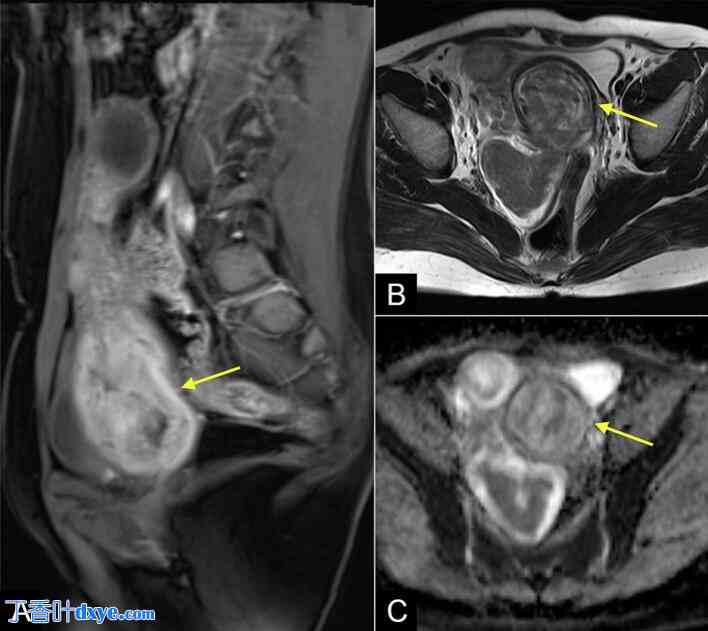

行胸腹部CT扫描,显示右心房、下腔静脉及右肝静脉内可见一巨大低密度、轻度强化肿块,可能侵犯肝脏VII-VIII段(图1)。子宫内亦可见多发肿块。双侧输卵管扩张并充满液体,右侧输尿管受压或粘连导致轻度肾积水。此外,肝VII段亦发现一结节,不能排除转移性病变。行盆腔MRI检查以筛查恶性肿瘤,结果显示多发性退行性子宫肌瘤(图2)。也考虑过子宫腺肌症合并平滑肌肉瘤的鉴别诊断,但可能性较小。脑部CT扫描未见脑部受累的证据。胸部CT未见肺部结节或肿块。

图1.

胸腹部CT显示右心房、下腔静脉和右肝静脉内可见一较大的低密度、轻度强化肿块(箭头):(A)轴位图像;(B)轴位图像,显示肝转移结节(箭头);(C)冠状位图像;(D)矢状位图像。